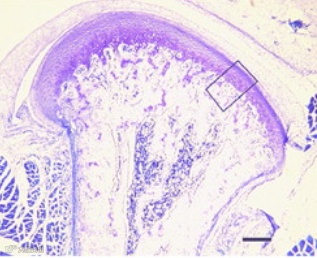

髁突的静态组织学结构

①结缔层(articular layer,A):是髁突最表面的结缔组织层,富含未分化的间充质细胞;

②静滞层(resting zone,R):软骨细胞形态较小,处于向成熟软骨细胞分化的最初期,状态稳定;

③扩增层(proliferative zone,P):该层内软骨细胞密集排列,细胞处于活跃增殖状态;

④成熟层(hypertrophic zone,H):细胞数量减少,形态饱满肥大;

⑤凋溃层(erosive zone,E):是髁突软骨与骨之间的交界区域,细胞凋溃,基质崩解,为骨开始形成的区域。

髁突的静态组织学结构是其动态生物学进程的反映,其核心机制是软骨内成骨。